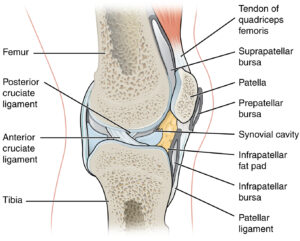

- Bursitis

- Knee Joint – Tendon, Ligaments, Bursa © J. Gordon Betts, Kelly A. Young, James A. Wise, Eddie Johnson, Brandon Poe, Dean H. Kruse, Oksana Korol, Jody E. Johnson, Mark Womble, Peter DeSaix is licensed under a CC BY (Attribution) license